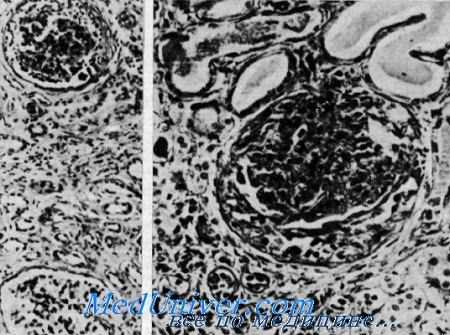

Нефрит и нейросенсорная глухота (синдром Альпорта). Сверху клубочек с утолщенной основной мембраной и слипшейся капсулой в противоположность почти нормальному клубочку внизу. Видны редкие клубочки, имеющие полулупиую форму, расширенные канальцы, содержащие белковые цилиндры. Утолщенная основная мембрана, окружающая атрофичные канальцы в области фиброза (из H. I. Krickstein et al.).